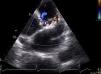

Uma reavaliação ecocardiográfica em janela paraesternal permitiu detetar dilatação do tronco da artéria pulmonar (34mm), com preservação do tamanho das cavidades direitas. Com Doppler identificou‐se fluxo laminar contínuo a drenar no segmento proximal do tronco da artéria pulmonar, com predomínio diastólico e velocidade máxima 1,0m/s (Figura 2), que corresponde ao local de drenagem da fístula coronária. Em relação ao trajeto da artéria descendente anterior, visualizaram‐se zonas de fluxo turbulento que correspondem à ramificação da fístula a este nível (Figura 3). A pressão estimada da artéria pulmonar era 28mmHg e não se identificaram outras anomalias congénitas.

Ecocardiograma transtorácico (plano paraesternal, eixo curto): à esquerda, com Doppler cor visualiza‐se fluxo laminar a drenar na região proximal do tronco da artéria pulmonar (seta amarela); observa‐se ainda pequeno fluxo de insuficiência pulmonar. À direita, Doppler contínuo revela que se trata de um fluxo sistodiastólico, com predomínio diastólico e com velocidade máxima de 1,0m/s.